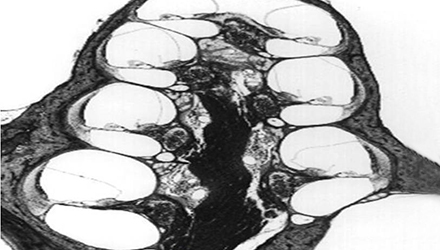

3、膜迷路破滅

膜迷路積水致膜迷路脹破,內(nèi)外淋巴液混合,刺激神經(jīng)感覺細胞導(dǎo)致眩暈、耳鳴、耳聾,裂口愈合則病變暫時恢復(fù)。下圖左為前庭膜膨大,右圖為前庭膜破裂,內(nèi)外淋巴交混。